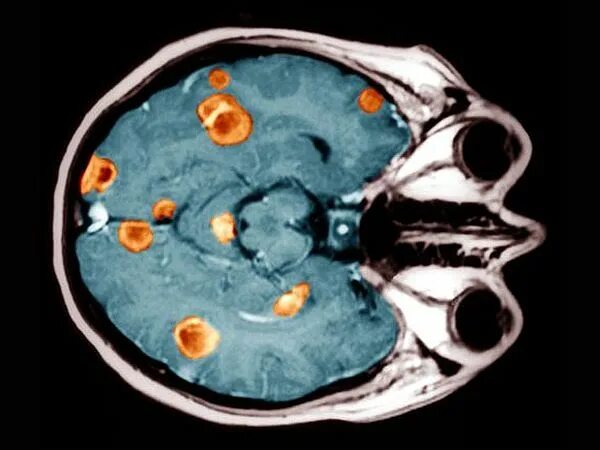

Отек мозга метастазы